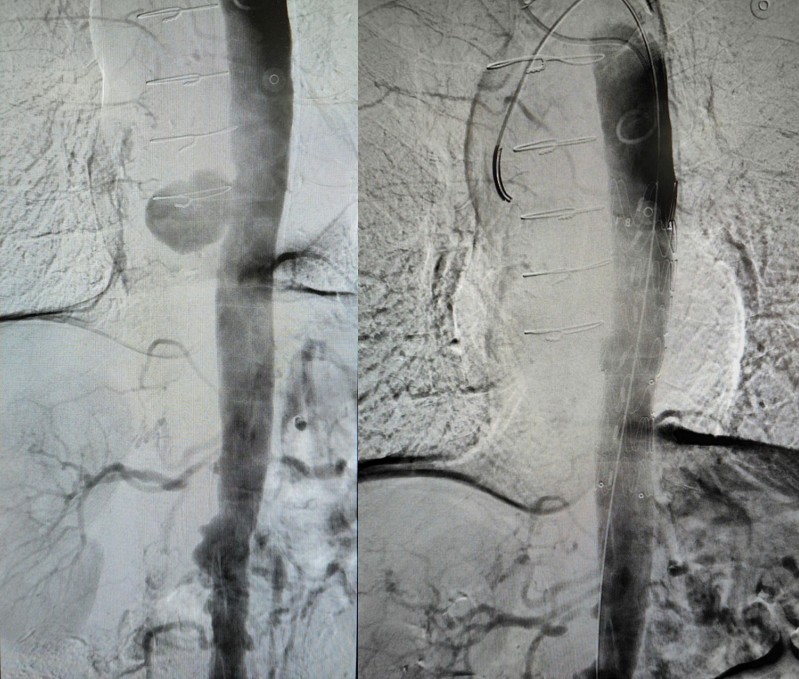

冬至前夕,我院血管介入科王偉迪團(tuán)隊(duì)密切配合,局麻下僅用時(shí)1小時(shí)完成胸主動(dòng)脈破裂動(dòng)脈瘤腔內(nèi)修手術(shù),患者正在康復(fù)之中。

主動(dòng)脈綜合征包括動(dòng)脈瘤、夾層、主動(dòng)脈瓣反流、主動(dòng)脈縮窄等。這些病變可能會(huì)導(dǎo)致嚴(yán)重的健康問題,甚至死亡,血管腔內(nèi)修復(fù)手術(shù)是首選治療方案 。